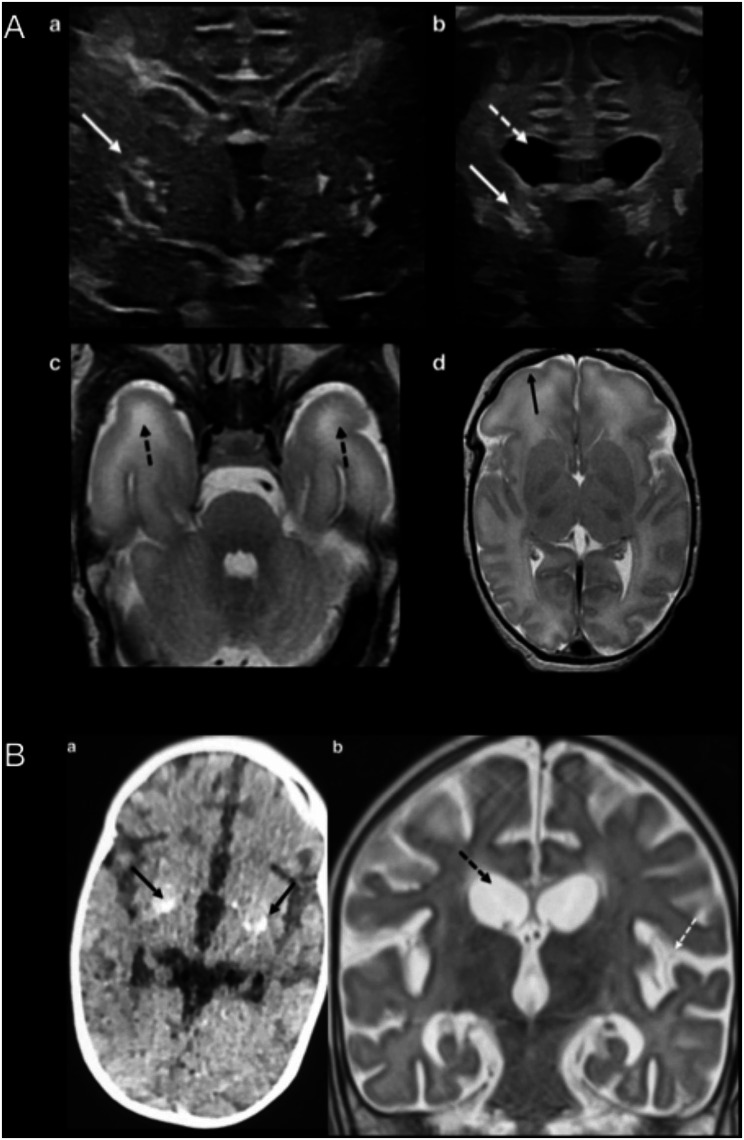

Case presentation: We present two siblings, a male neonate with congenital petechial rash, severe thrombopenia and generalized hypotonia and his deceased sister who had normal development until 5 months of age, when she suffered acute encephalopathy. We describe the clinical course, complementary examinations and follow-up with early treatment of the newborn with ruxolitinib. The homozygous variant c.2908G > A (p.Ala970Thr) in the ADAR gene was found in both siblings, parents were heterozygous carriers.

Conclusions: The homozygous variant c.2908G > A (p.Ala970Thr) in the ADAR gene causes Aicardi-Goutières Syndrome type 6. Intrafamilial phenotypic spectrum of the disease varies among individuals with the same pathogenic variant. Early initiation of ruxolitinib improved systemic signs but did not prevent the progression of neurological disease.